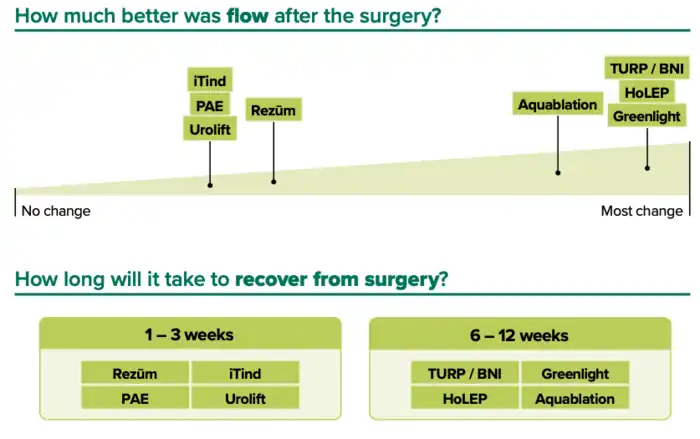

- ^ a b c d e f g "NHS England » Decision support tool: making a decision about enlarged prostate (BPE)". www.england.nhs.uk. Retrieved 8 September 2024.